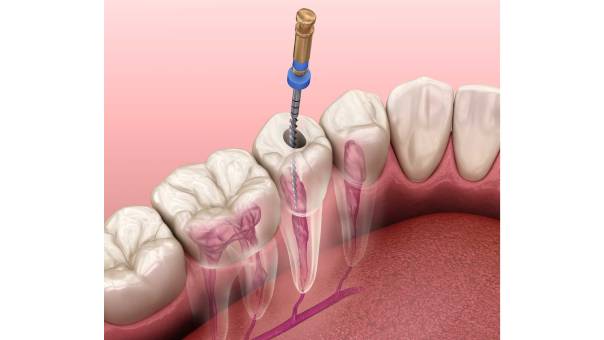

What is a Root Canal Treatment?A root canal treatment is a dental procedure designed to remove infected or damaged pulp tissue from within a tooth. The pulp is the innermost part of the tooth, containing nerves, blood vessels, and connective tissue. When it becomes infected due to deep decay, cracks, or trauma, it can cause severe pain, swelling, and eventually lead to tooth loss if left untreated.

The goal of RCT is to clean the infected area, disinfect the canals, and seal them to prevent further bacterial invasion. This allows the tooth to be preserved rather than extracted.

A standard RCT involves the following stages: